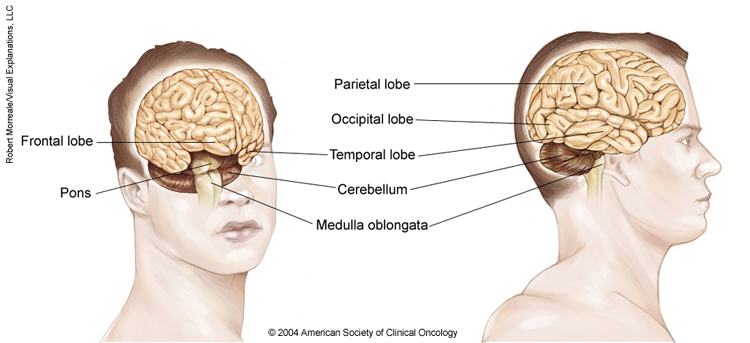

Anatomy of the brain

The brain is made up of 3 main parts: the cerebrum, the cerebellum, and the brain stem. The meninges, which surround the brain, are also considered part of the brain.

The cerebrum. This is the largest part of the brain. It contains 2 cerebral hemispheres on either side of the brain that each control the opposite side of the body. It is divided into 4 lobes where specific functions occur:

The frontal lobe controls reasoning, emotions, problem-solving, expressive speech, and movement.

The parietal lobe controls the sensations of touch, such as pressure, pain, and temperature. It also controls parts of speech, visual-spatial orientation, and calculation.

The temporal lobe controls memory, special senses such as hearing, and the ability to understand spoken or written words.

The occipital lobe controls vision.

The cerebellum. The cerebellum is located at the back part of the brain below the cerebrum. It is responsible for coordination and balance, and it controls functions on the same side of the body.

The brain stem. This is the portion of the brain that connects to the spinal cord and the cerebellum. It controls involuntary functions essential for life, such as the beating of the heart and breathing. Messages for the functions controlled by the cerebrum and cerebellum travel through the brain stem to the body.

The meninges. These are the membranes that surround and protect the brain and spinal cord. There are 3 meningeal layers, called the dura mater, arachnoid, and pia mater. The cerebrospinal fluid (CSF) is made near the center of the brain, in the lateral ventricles. CSF circulates around the brain and spinal cord between the arachnoid and pia layers.

Brain lobes

Each side of your brain contains four lobes. The frontal lobe is important for cognitive functions and control of voluntary movement or activity. The parietal lobe processes information about temperature, taste, touch and movement, while the occipital lobe is primarily responsible for vision. The temporal lobe processes memories, integrating them with sensations of taste, sound, sight and touch.